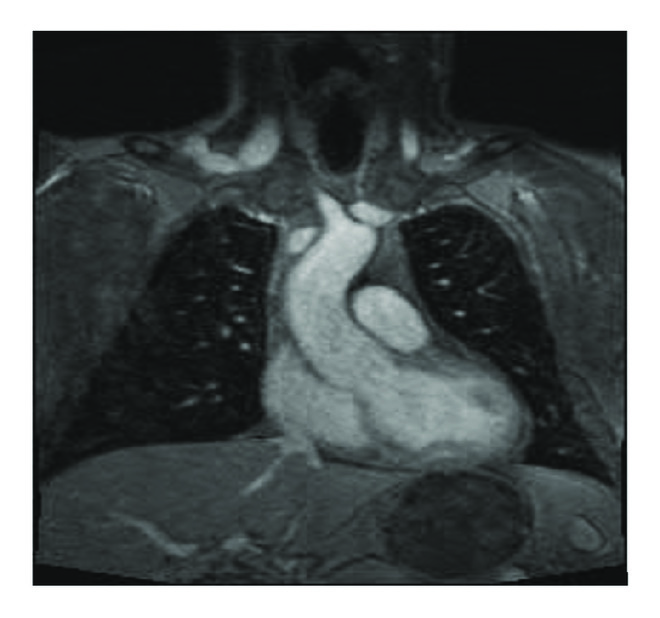

Our proband is a 43-year-old male of northern European descent who initially presented with acute onset left leg cramping pain that lasted for several days. The pain was associated with numbness in his left leg and nausea. His past medical history was significant for mitral valve prolapse, aortic root dilation umbilical hernia left anterior cruciate ligament (ACL) rupture, and severe myopia corrected with LASIK surgery. Family history revealed rheumatic heart disease in his mother, necessitating mitral valve repair due to mitral valve prolapse with severe regurgitation. Upon examination, his popliteal arterial pulses were 4+ bilateral, bounding. His height was 196 cm, with an increased arm span-height ratio of 1.07. He had a mild pectus carinatum deformity, mild scoliosis positive wrist and thumb sign, pes planus, and mild skin striae. A Doppler ultrasound was performed by his primary care physician (PCP), which ruled out deep venous thrombosis (DVT); however, it revealed a large left popliteal artery aneurysm with thrombus that measured 6.3 × 3.1 × 3.4 cm. He underwent a CT angiogram that showed normal abdominal aorta as well as common iliac arteries. However it showed bilateral popliteal artery aneurysms measuring 3.6 × 4 cm in the left side and 3 × 2.8 cm in the right side (Figure 3). After repairing of his left popliteal artery aneurysm with bovine carotid interposition via posterior approach, he was sent for cardiac and genetic evaluations. He underwent a MRI exam of the heart with and without intravenous gadolinium contrast administration (Figure 2) which showed mild bileaflet mitral valve prolapse and aortic root dilation (measuring 46 mm at the level of the sinuses of Valsalva). The patient has been prescribed metoprolol tartrate and losartan to control his aortic root disease and was to undergo elective aortic repair when the aortic dimension becomes near to or reaches 50 mm. A diagnosis of Marfan syndrome was made based on the revised Ghent criteria as the proband had aortic root dilation (-score: 3.72) and a systemic score of 12 (Table 1). His diagnosis was further confirmed after undergoing FBN1 sequencing and deletion/duplication analysis, which detected a novel pathogenic variant in gene FBN1, denoted by c.5872 T>A (p.Cys1958Ser) (Figure 1).